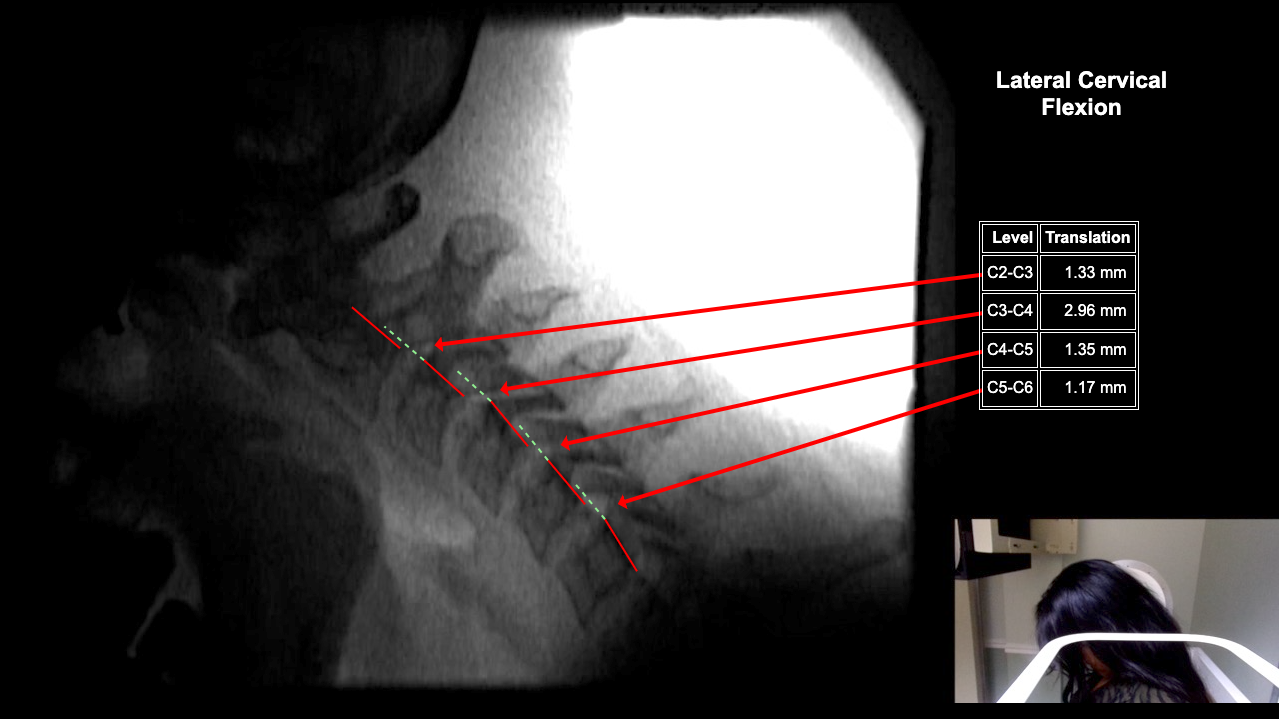

Image Name Image Type Image